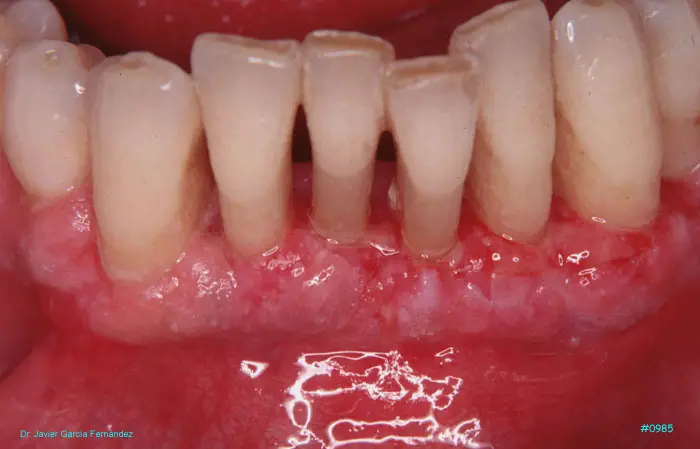

Atlas of Surgical Techniques in Periodontics. Chapter III. Atlas de Técnicas Quirúrgicas en Periodoncia